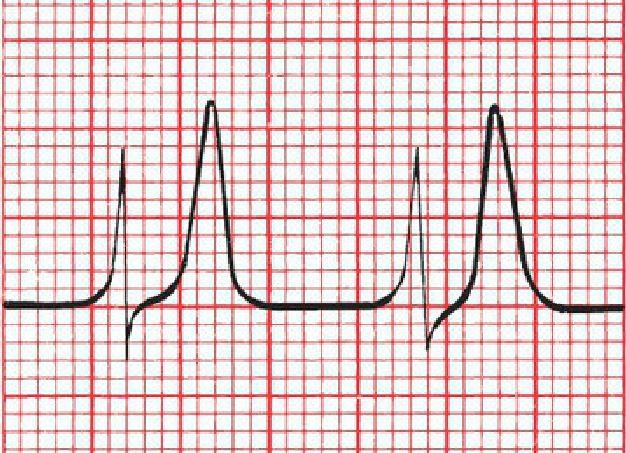

What kind of electrolyte disturbance will produce the following ECG?

The peaked T waves of hyperkalemia.